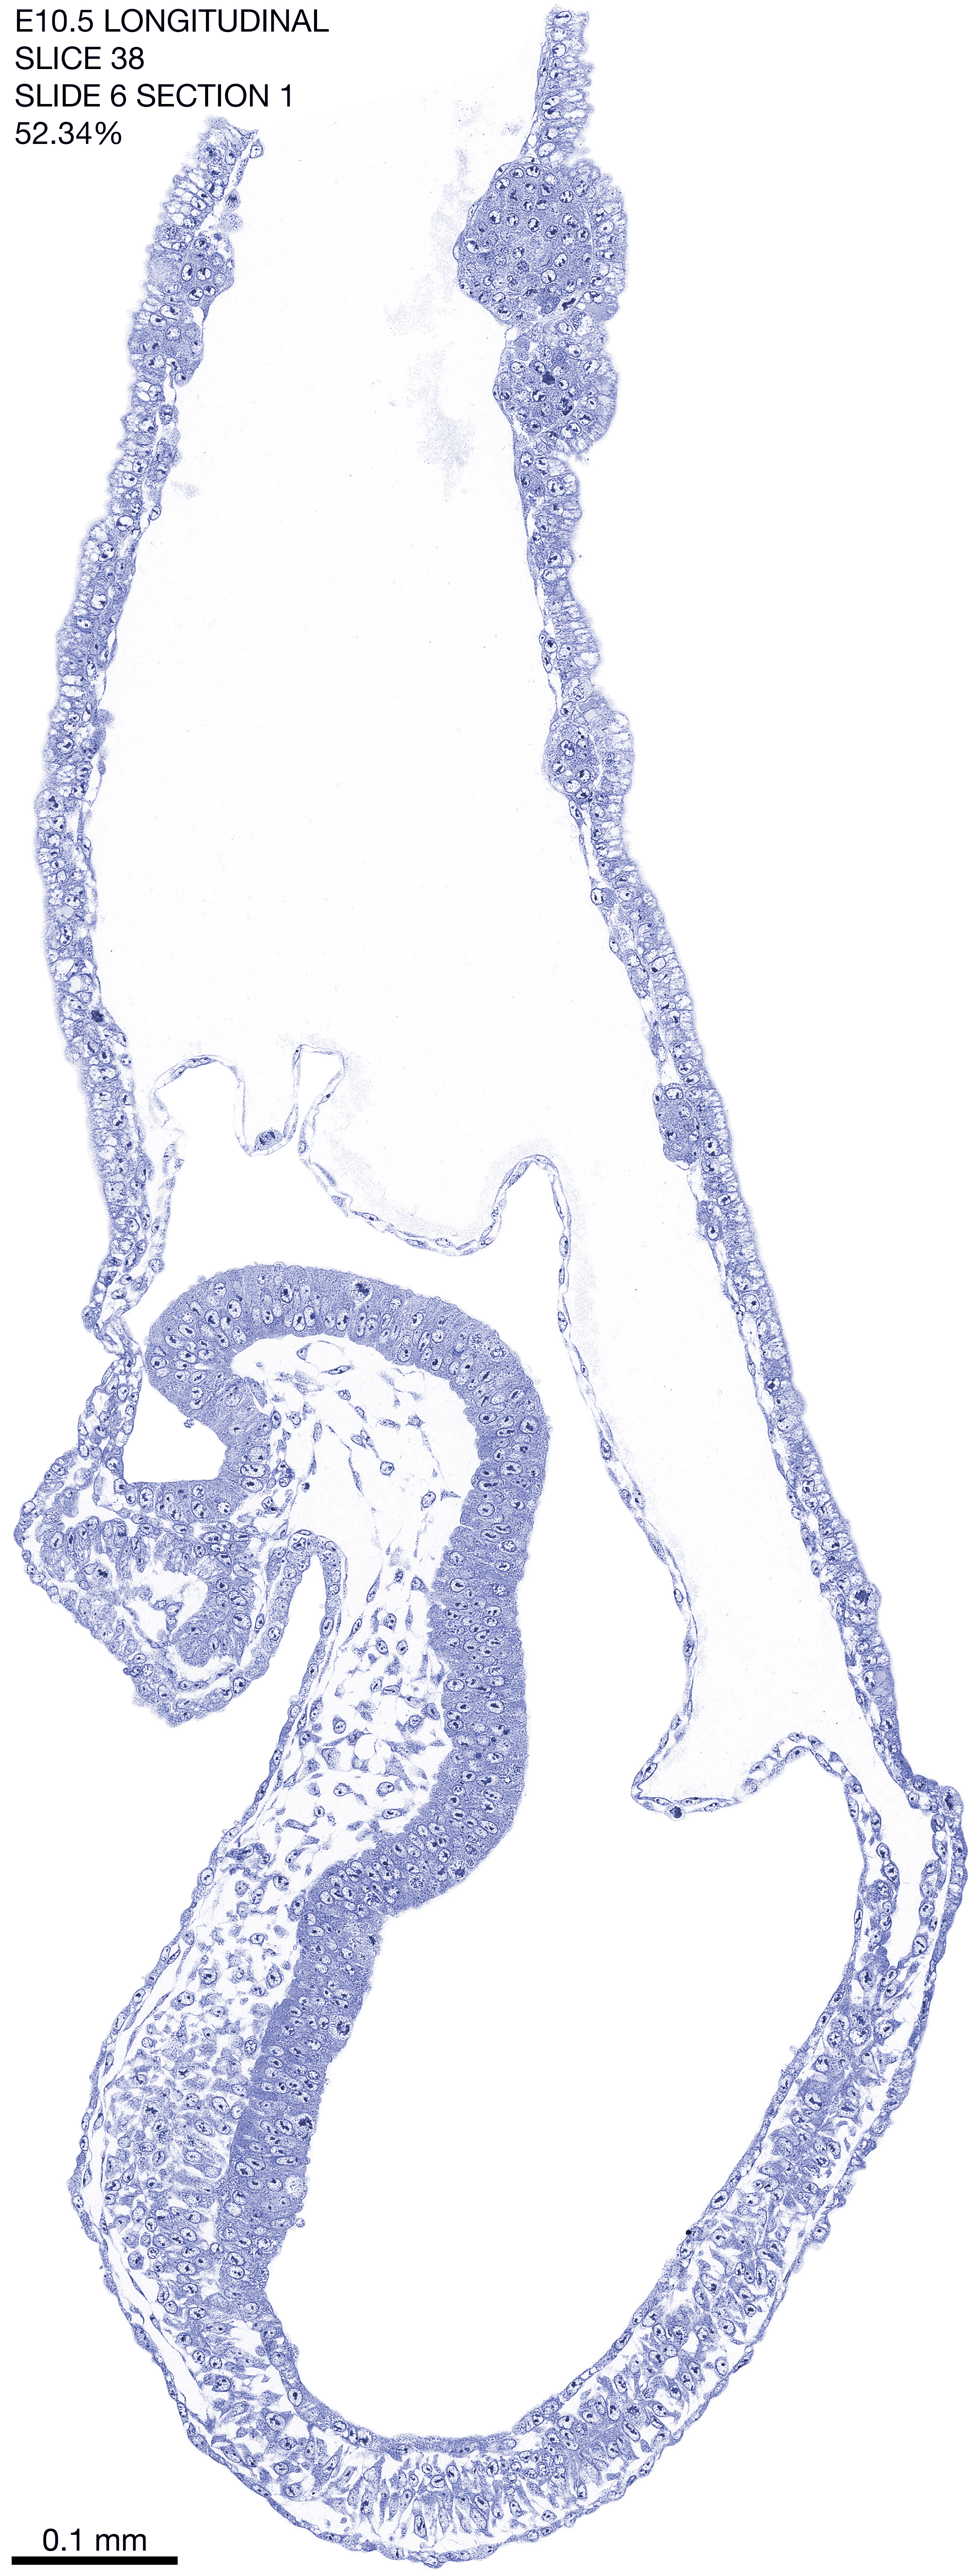

E10.5 Longitudianal Archive This page contains jpg files of ALL SLICES (each 3µm thick) that were scanned of the E10.5 longitudinally cut specimen. Download: Large | High Res Download: Large | High Res Download: Large | High Res Download: Large | High Res Download: Large | High Res Download: Large | High Res Download: Large | High Res Download: Large | High Res Download: Large | High Res Download: Large | High Res Download: Large | High Res Download: Large | High Res Download: Large | High Res Download: Large | High Res Download: Large | High Res Download: Large | High Res Download: Large | High Res Download: Large | High Res Download: Large | High Res Download: Large | High Res Download: Large | High Res Download: Large | High Res Download: Large | High Res Download: Large | High Res Download: Large | High Res Download: Large | High Res Download: Large | High Res Download: Large | High Res Download: Large | High Res Download: Large | High Res Download: Large | High Res Download: Large | High Res Download: Large | High Res Download: Large | High Res Download: Large | High Res Download: Large | High Res Download: Large | High Res Download: Large | High Res Download: Large | High Res Download: Large | High Res Download: Large | High Res Download: Large | High Res Download: Large | High Res Download: Large | High Res Download: Large | High Res Download: Large | High Res Download: Large | High Res Download: Large | High Res Download: Large | High Res Download: Large | High Res Download: Large | High Res Download: Large | High Res Download: Large | High Res Download: Large | High Res Download: Large | High Res Download: Large | High Res Download: Large | High Res Download: Large | High Res